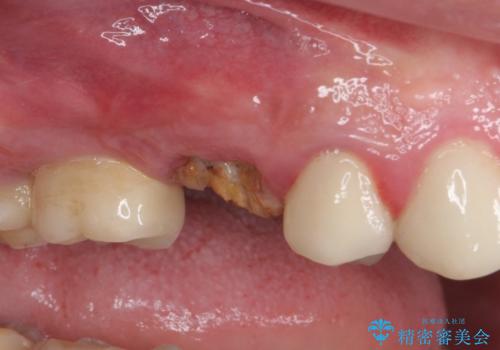

折れてしまった歯 インプラントによる補綴治療

- 咬合力により歯が割れてしまった方のインプラント治療です。

抜歯後4ヶ月ほど待ち、後方のインプラントと同一メーカーのインプラントを埋入することとしました。